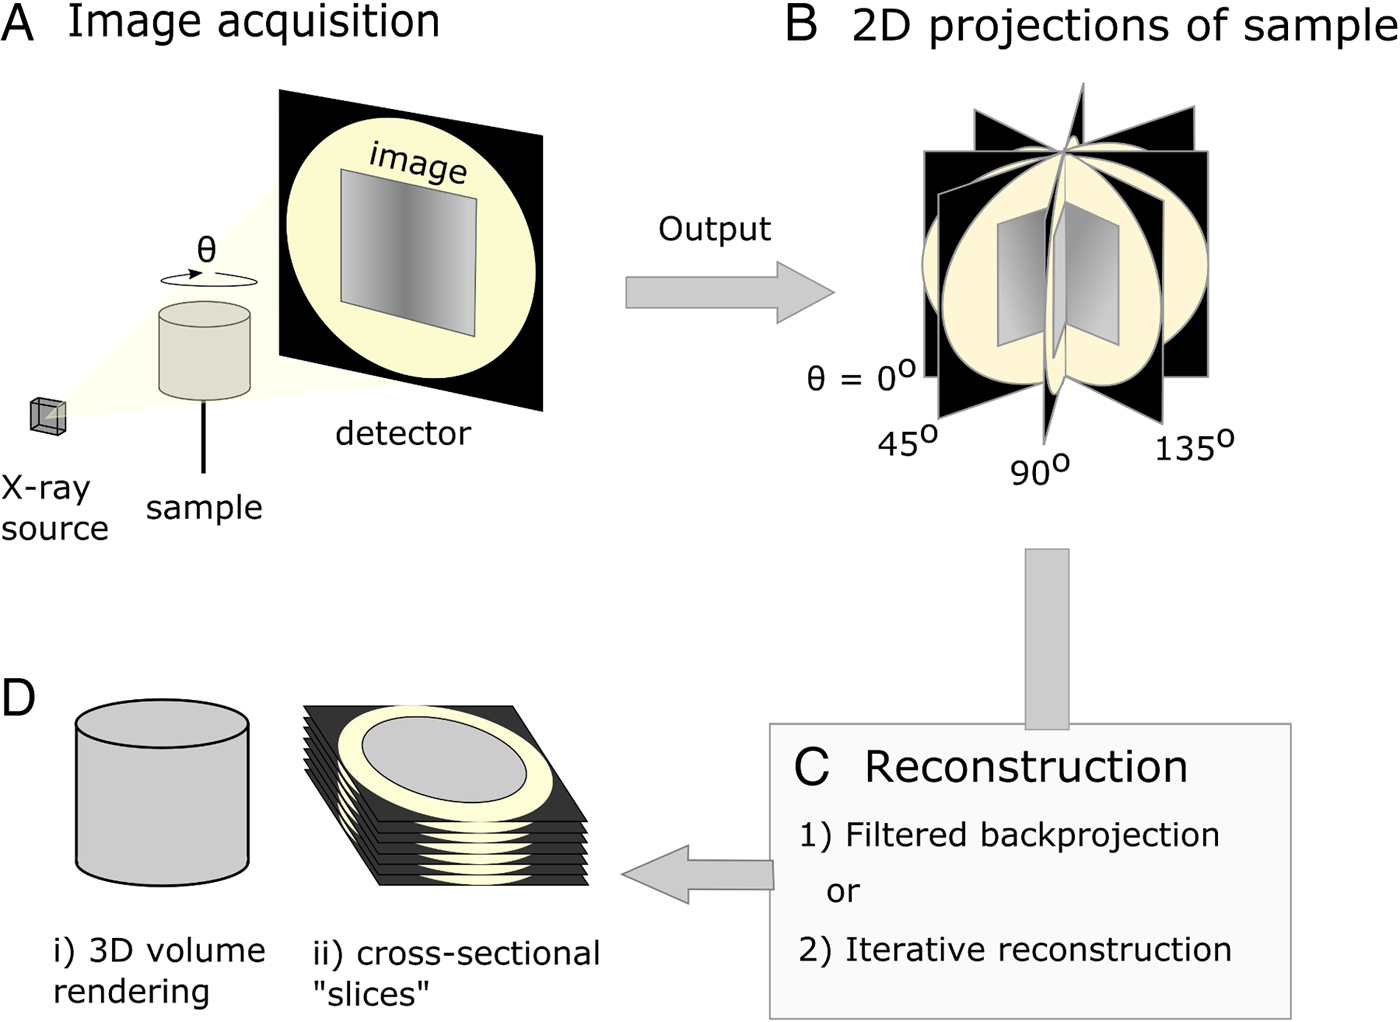

X-ray μCT was developed in the early 1980s (Dover et al. Reference Dover, Elliott and Kernaghan1981; Elliott et al. Reference Elliott, Dowker and Knight1981; Elliott and Dover, Reference Elliott and Dover1982) and could be described as the microscopic cousin of the clinical computed tomography (CT) scanners used to examine human patients in hospitals today. However, whereas medical scanners usually have resolutions in the mm range, μCT systems typically achieve resolutions in the 1–100 µm range. When imaging using X-ray tomography, many (typically between 500 and 3000) 2D projections (digital radiographs) of a sample are collected from many different angles using penetrating X-rays. Following their acquisition, a 3D image of the absorptive power of the sample is reconstructed computationally from the 2D projections (Fig. 1). Tomographic images can also be reconstructed from images produced with gamma rays (Ter-Pogossian et al. Reference Ter-Pogossian, Phelps, Hoffman and Mullani1975), neutrons (Winkler, Reference Winkler2006), electrons (Crowther et al. Reference Crowther, DeRosier and Klug1970) or visible light (Sharpe et al. Reference Sharpe, Ahlgren, Perry, Hill, Ross, Hecksher-Sørensen, Baldock and Davidson2002). However, X-rays are often chosen based on the balance between penetration of, and attenuation by, the sample, such that sufficient contrast (glossary, Box 1) can permit the differentiation of internal features of interest. The contrast results from the differential attenuation of X-rays, as determined by the attenuation coefficient of the constituent materials. If a material is dense, or includes heavy elements, more X-rays will be attenuated and transmittance will be reduced. Upon acquisition of the data, the 3D volume can be interrogated by examining key virtual cross-sectional images or the whole image stack. In many cases quantification of features in the imaged volume requires the application of ‘segmentation’ workflows, a process by which domains/features of interest within the sample are virtually distinguished and labelled. Subsequently, visualization and quantitative analysis of the number, morphology and distribution of the features can then be undertaken (Maire and Withers, Reference Maire and Withers2014).

Fig. 1. Diagrammatic representation of X-ray micro-computed tomography workflow. (A) Basic illustration of tomographic apparatus, including the X-ray source, detector and sample. Projection images are made as the sample is rotated at increments through θ. (B) The raw output of the tomogram is a series of projections of the sample taken at different angles. (C) Projections are digitally ‘reconstructed’; two commonly used approaches are filtered backprojection and iterative reconstruction. Reconstruction algorithms output a dataset which is suitable for analysis. (D) The sample may be viewed in a virtual environment in a variety of ways, including as a 3D rendered volume (Di). Alternatively, 2D cross-sections, or ‘slices’ (Dii), of the sample may be viewed.